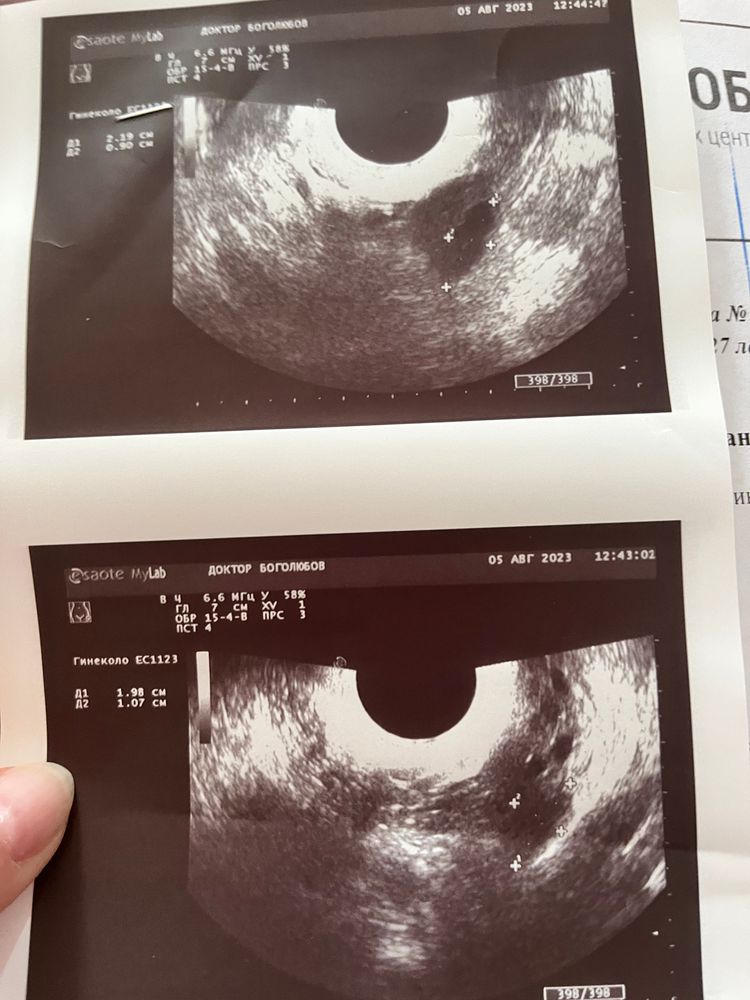

была на узи на 20 дц (так как с мужем ездили в отпуск, не могла сделать раньше) сказали что-то видят в правом и левом яичниках. Вроде как доминантные фолики, а вроде и желтое тело, или вообще «может это дырочки после дриллинга». Этот узист вызвал у меня недоверие, я пошла на сл. День в другую клинику и сделала узи там. Врач сказала, что не видит никаких ДФ и что овуляции вообще не было, и жидности в позадиматочном пространстве нет. Эндик всего 6мм. Узи подкрепляю. Третье фото это узи на 21дц. Подскажите пожалуйста, что это было?

Первый узист, похоже, принял два фолликула за один большой, разделила их на маленькие как мне кажется